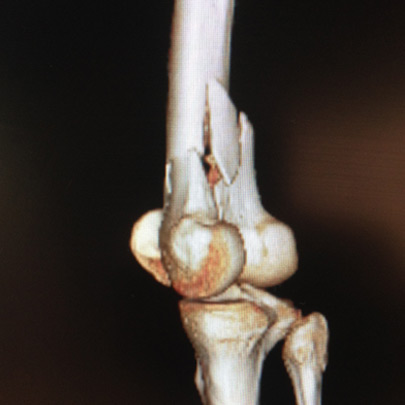

Fracturas y luxaciones

Lesiones complejas

Cirugía de codo